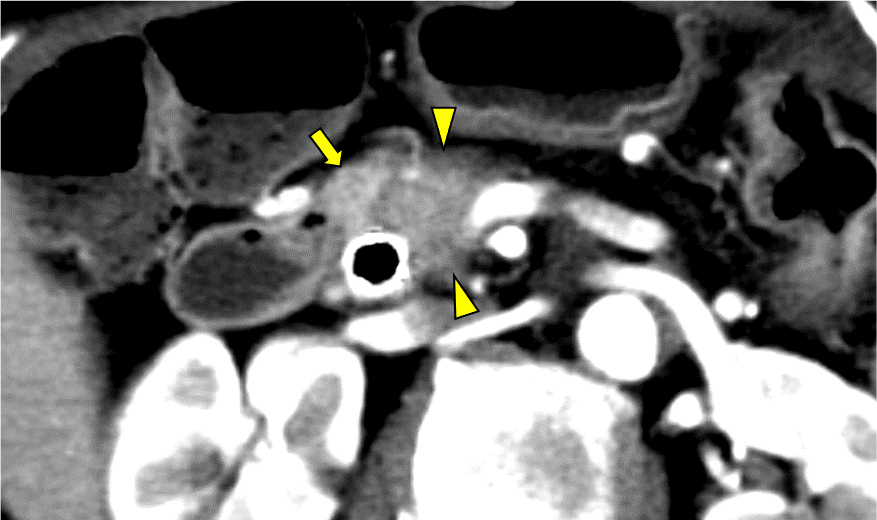

図6.造影CT 平衡相 Axial像 40keV

平衡相では、背景の正常膵実質(矢印)と比較して膵癌病変(矢頭)には遷延性の造影効果がみられる。40keVの画像ではこの遷延性の造影効果がより明瞭に描出されている。